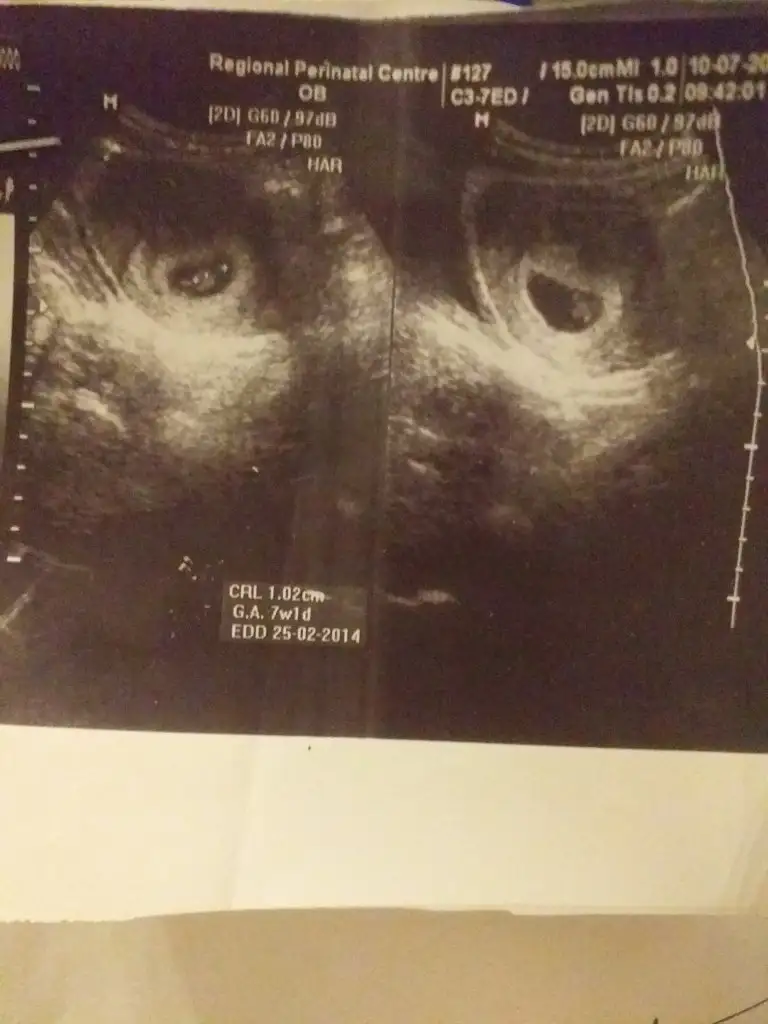

En dogru kese usg 5 hafta dr kesede bebek yokken yolk sac gösteren usg foto veriyor o daha cok dogru bir usgBak canim ikiside ayni anda cekilmis usg biri yakin pozuEki Görüntüle 2553167 Eki Görüntüle 2553167 syon biri uzak .karindan usg 7haftalik

Bu benim 5.hafta vajinal ultrasonum ilk fotoğraftaki. altta 6. hafta diyor ama benim 1 hafta geç döllenme.

2.foto 6.hafta karından ultrason.